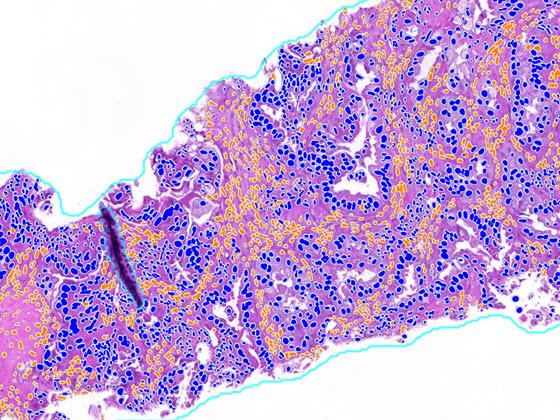

After selecting an image, view the H&E slide in the viewer and the Lung Macrodissect AI results. Results include overlays and quantitative results. The first set of overlays prepare the tissue for analysis by identifying areas of analyzable tissue. The next overlay identifies areas of tumor in the tissue, with the tumor density heatmap highlighting the densest areas of tumor. With the assistance of the heatmap, users identify the dissection area by drawing a region of interest with immediate quantitative feedback on the number of all cells and tumor cells in the region to ensure proper sampling.